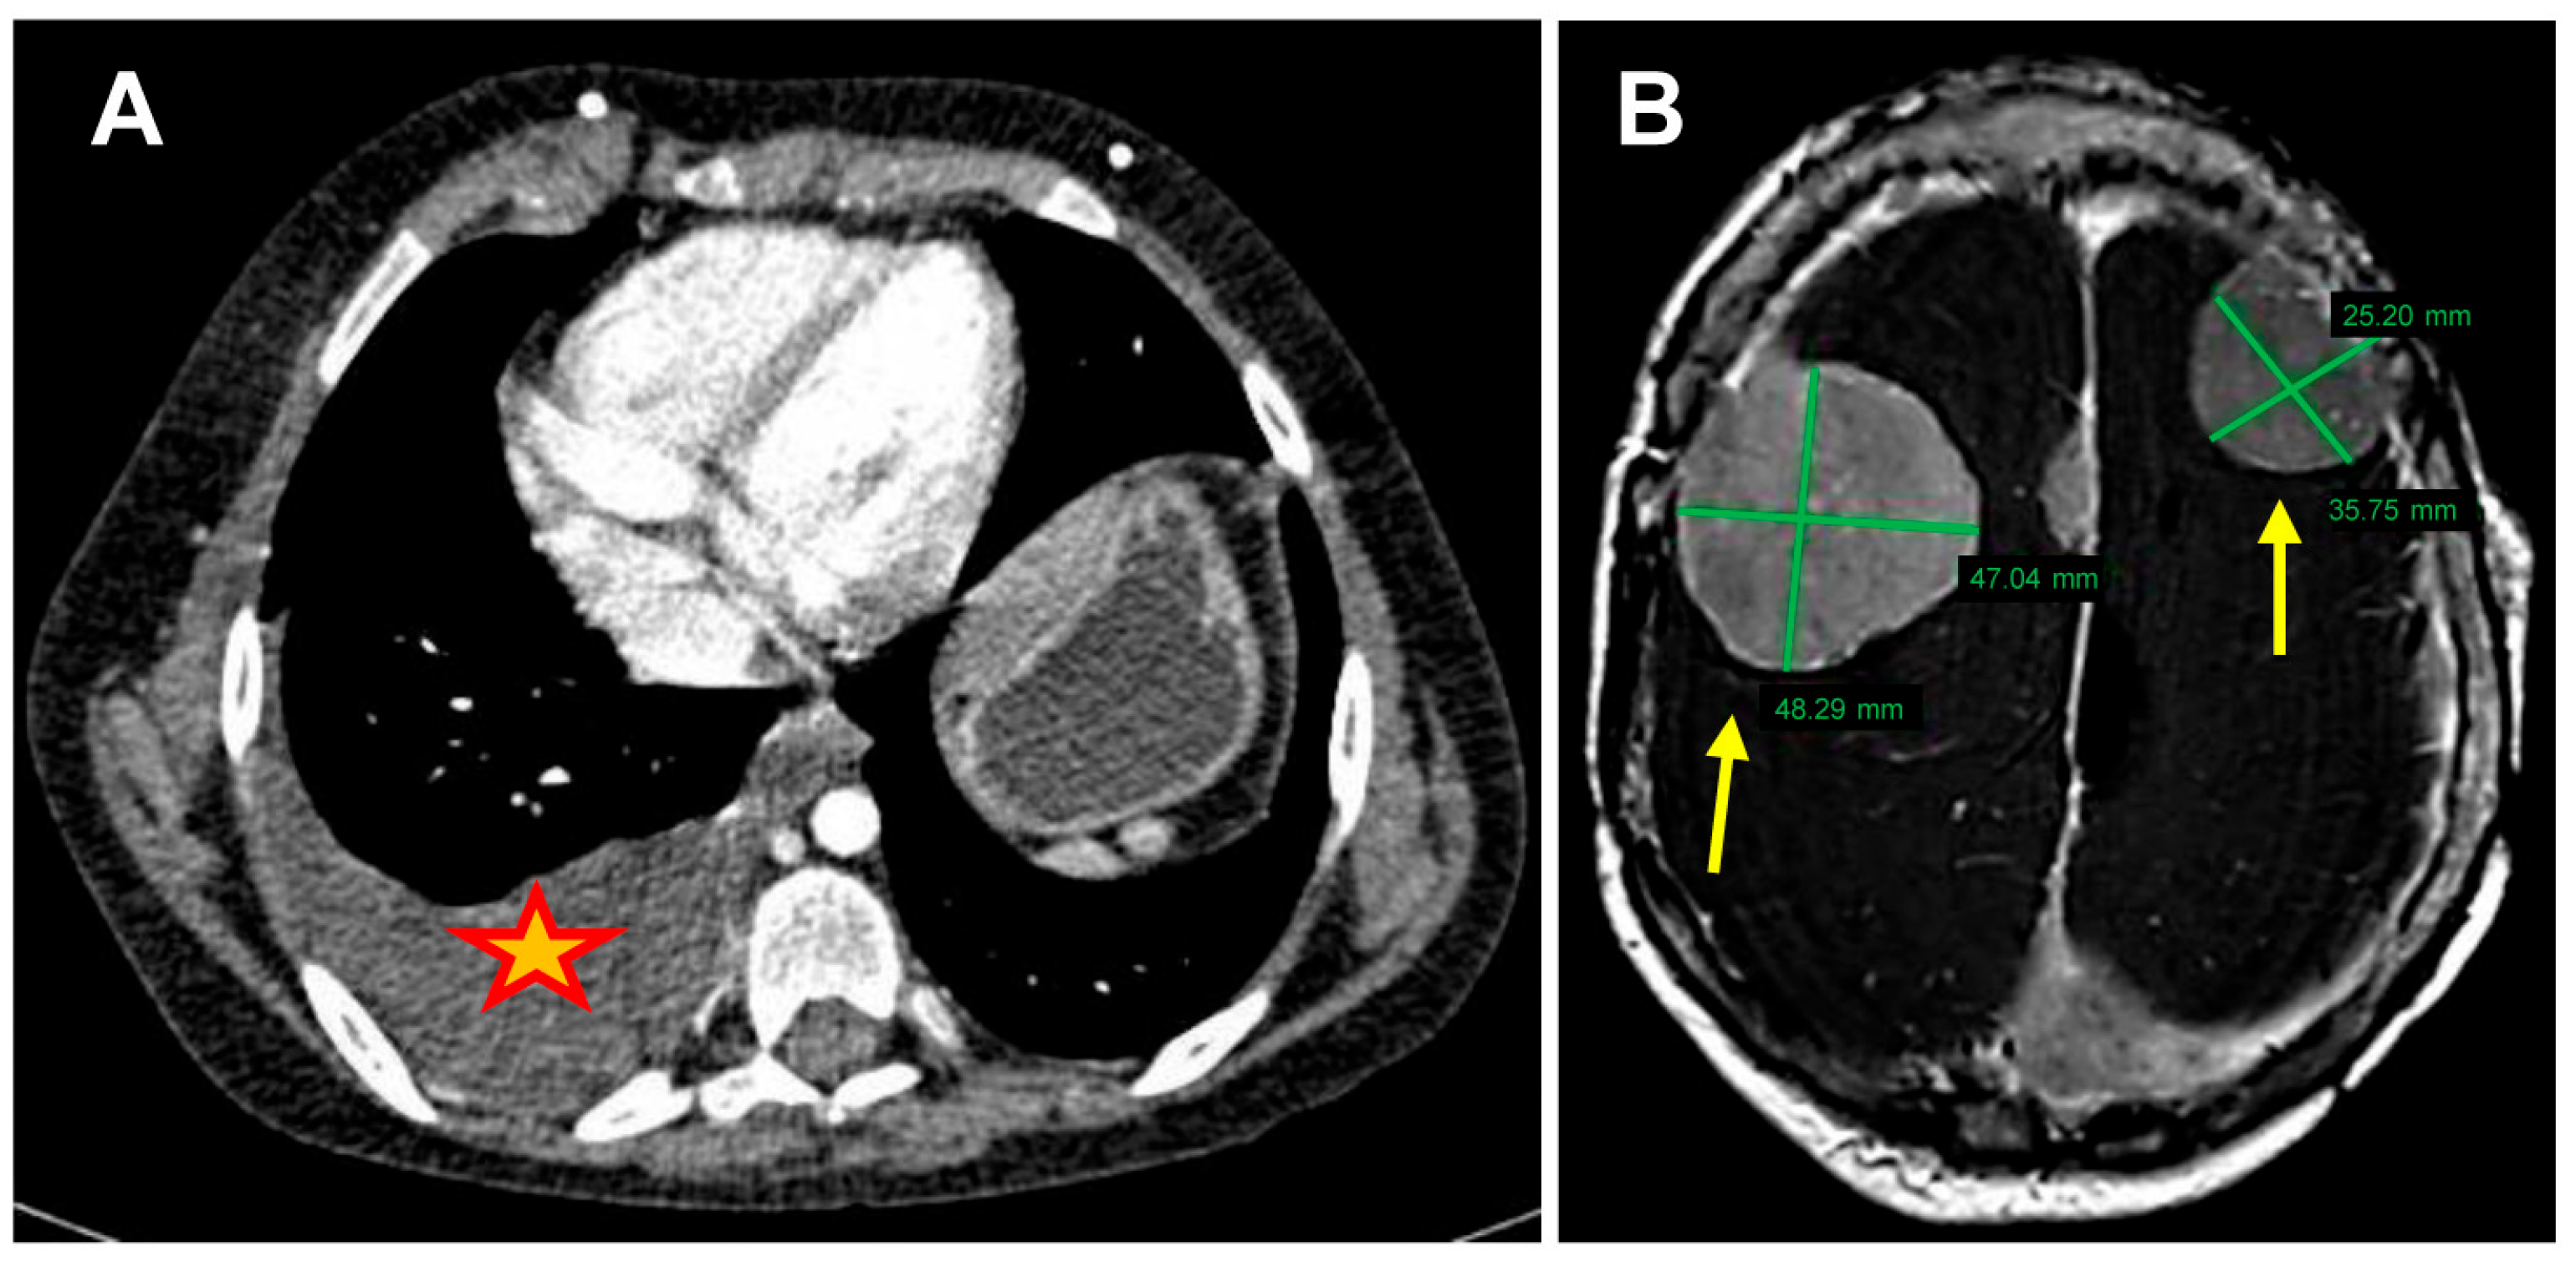

2.1. Patient Information